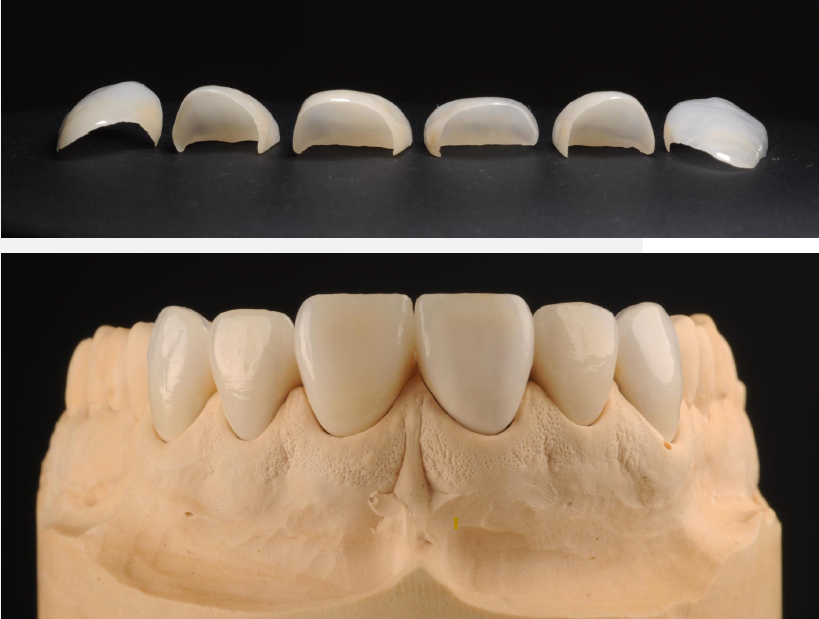

Front and underneith image of glass-ceramic veneers.

Layered felspathic glass-ceramic veneers.

Close-up of the upper jaw with trying on the veneers

Try-in of veneers.